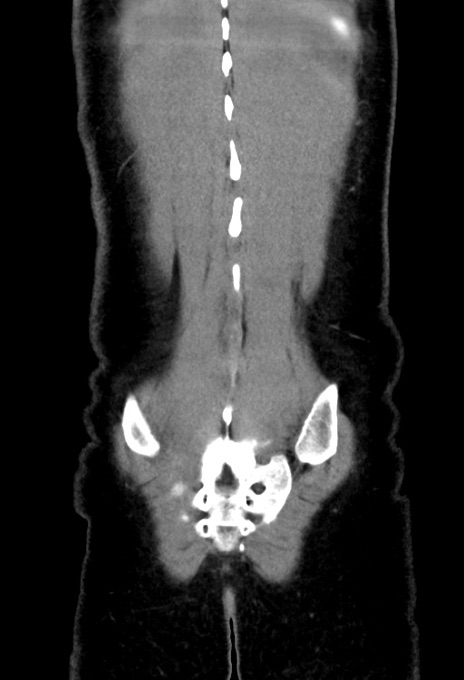

症例17(冠状断像)

【症例】20歳代女性

【主訴】嘔吐、下腹部痛

【現病歴】昨日夕食後に嘔吐し下腹部痛が出現。本日になっても嘔吐持続し改善しないため来院。

【身体所見】意識清明、BT 37.2℃、BP 108/67mmHg、腹部:平坦、やや硬、下腹部正中から右にかけて圧痛あり、反跳痛軽度あり、tapping pain(+)。

【データ】WBC 13600、CRP 14.94

横断像